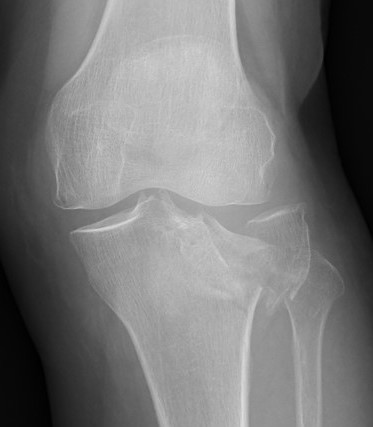

Schatzker Classification

I. Lateral Spilt

- seen in young patient

- lateral meniscus can be incarcerated in fracture

II. Lateral Split Depression

- often seen in young patients with high energy injuries

- vary in severity

III. Lateral Depression

- central depression usually seen in elderly

- have to create lateral cortical window in order to elevate fragment

IV. Medial plateau & intercondylar eminence

- high velocity injury associated with ACL / LCL / CPN injury

- can be low injury / osteoporotic and often unreconstructable

V. Bi-condylar + intact metaphysis

- unstable

- requires ORIF

VI. Bi-condylar + metaphyseal fracture

- fracture separating metaphysis from diaphysis

- highest incidence of vascular injury